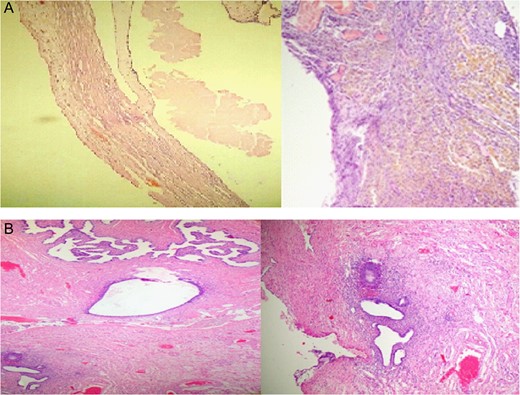

Ultrasound and computed tomography (CT) were normal except for a pelvic heterogeneous mass with some calcifications adjacent to and causing an impression on the bladder. The mass measured 13 × 8.5 cm (Fig. 2).

Surgery was scheduled, abdominal exploration was performed and a big mass was detected on the right ovary, which was then removed. Several cysts were found on the left ovary as well, one of which was filled with brown thick fluid.

A Uterine fibroid was found and removed after separating it from the uterus.

Neither ascites nor metastases were found.

The final pathological results were serous cystadenoma, hyalinized and necrotic with foci of endometriosis measuring 15 × 10 × 7 cm, leiomyoma measuring 1.5 × 1.3 × 1 cm (Fig. 3)